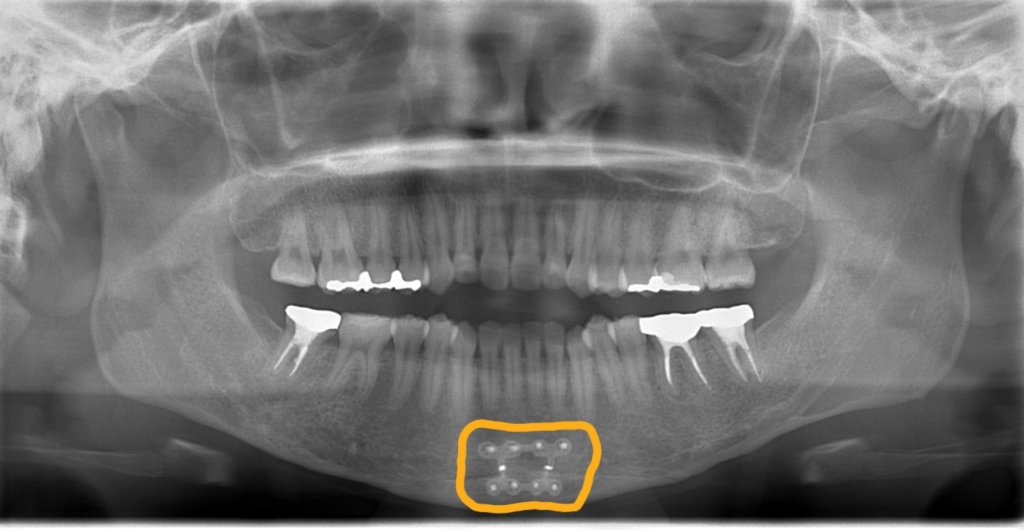

上の歯列がきれいに並んで、アンカースクリューを植立する目途がついたので、上顎の口蓋正中部、臼歯部と前歯部の頬側辺りにアンカースクリューを植立しました。(計6本)

奥歯の圧下による下顎の反時計回りの回転を狙っています